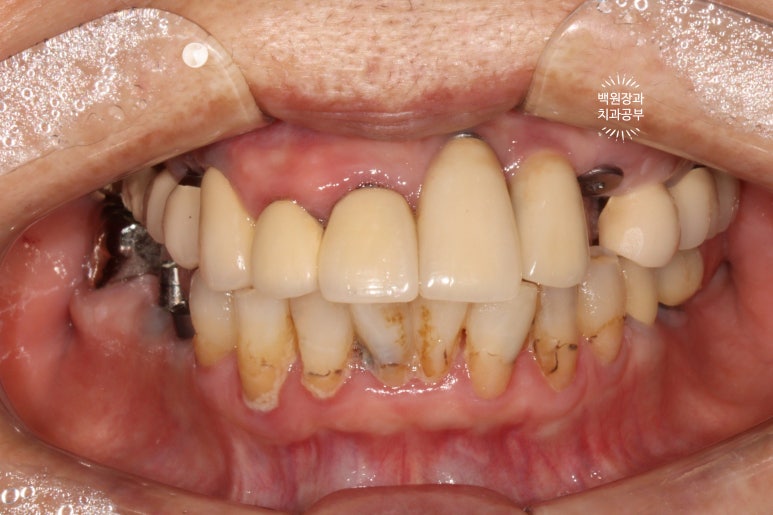

Before & After

정면 사진이 가장 드라마틱한데요,

일단 철저한 스케일링과 잇몸치료 그리고 함께 했던 착색제거술로 전반적으로 깨끗해진 구강내 환경을 보실 수 있어요!!! 다만, 아래 앞니에 있던 치아 목부위 레진들의 착색은 완전히 제거하지 못했답니다... 이는 다시 떼워야 해결이 되어요!

그리고 아래 앞니 한 곳은 지르코니아 크라운으로 씌워드렸고, 가지런히 깨끗깨끗~

위턱의 씹는면을 보시면, 스트라우만 임플란트로 아주 깔끔히 치료된 것을 보실 수 있습니다.

옛날에 치료받았던 스트라우만 임플란트는 이제 오래되어... 조금 깨지도 닳은 것은 보이나, 사실 기능하는데는 문제가 없었어요. 20년이 넘었음에도 이렇게 훌륭한 임상결과를 보이는 스트라우만 임플란트. 정말 최고임을 직접 보여주고 있었습니다. 진짜 올타임 넘버원 임플란트입니다.

아래 또한 깔끔하고 예쁘게 임플란트 크라운이 제작되었어요. 특징이라면 기존의 임플란트와 보철물을 묶어서 제작해드림으로써 음식이 끼는 것을 확실히 막아드렸다는 것입니다!